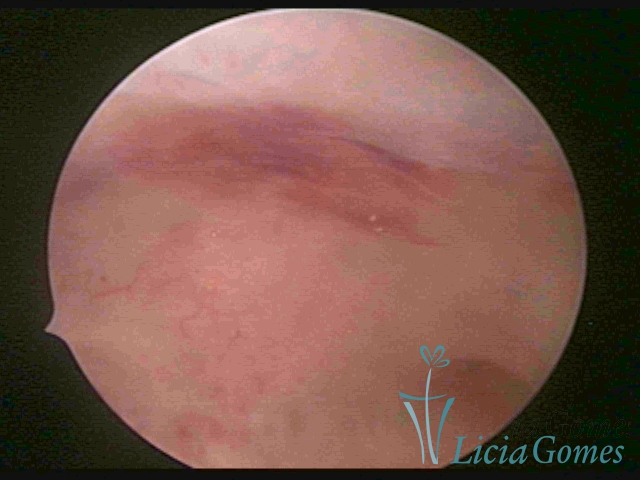

ENDOMETRITE CRÔNICA

A superfície do endométrio pode exibir alterações como um pontilhado vermelho formando novelos vasculares, o endométrio liso e hiper-vascularizado, ou com áreas vermelhas de forma intensa, com limites precisos e pontilhados branco amarelados no seu interior dando um aspecto “CASCA DE MORANGO” e uma coloração amarela pálida das comissuras fúndicas e laterais, em contraste com o vermelho intenso das paredes.